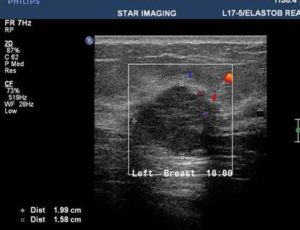

39yr old lady with history of lump in the left breast UIQ, No previous imaging done. No positive family history for CA Breast/Ovary. Pre-Menopausal Status.

Mammography- Fairly well circumscribed predominantly sold lesion in the left breast UIQ with partially obscured margins. No spiculations. No associated microcalcifications noted. Sonography: Well defined hypoechoiec lesion with smooth margins.

Low-grade Mucinous Carcinoma ER?PR- +ve HER-2 NEU -VE